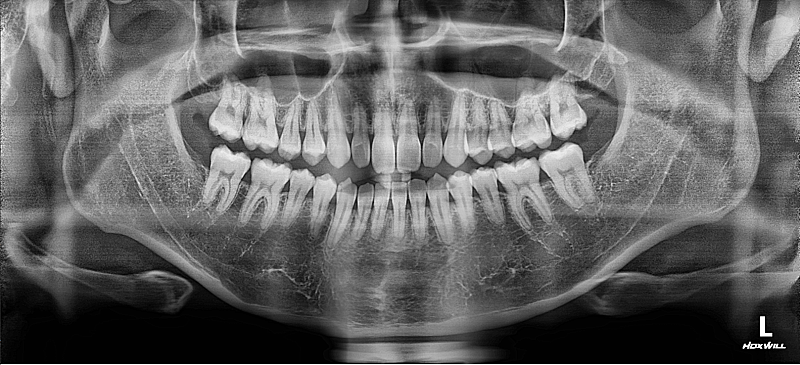

약간 비대칭이 있긴한데... 치아중심선 맞추기랑 앞니 부분적으로 절단교합이 있어서 교정할려고 해요

인비절라인으로 하면 1년 정도면 된다고 하는데 투명교정 하게되면 치아중심선이랑 12번치아 앞니 교합 교정, 전체적 치아가 살짝 틀어진거 교정 효과 볼 수 있을까요?

• 1번 째 사진